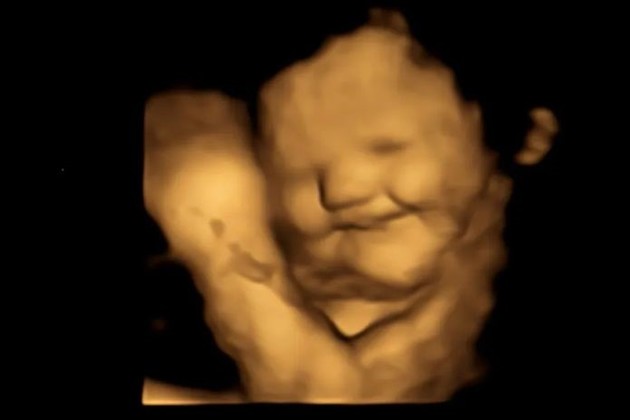

Los fetos crean más "cara de risa" en el útero cuando se exponen al sabor de las zanahorias que consume su madre y crean más "cara de llanto" cuando se exponen al repollo, según un estudio publicado este miércoles en la revista académica Psychological Science.

Mientras que el sabor de la zanahoria puede ser descrito como "dulce" por los adultos, se eligió el kale porque transmite más amargor a los bebés que otras verduras verdes como las espinacas, el brócoli o los espárragos, según el estudio. Tras un periodo de espera de 20 minutos después del consumo, las mujeres se sometieron a ecografías en 4D, que se compararon con imágenes en 2D de los fetos.

Los tirones de las comisuras de los labios, que sugieren una sonrisa o una risa, fueron significativamente mayores en el grupo de la zanahoria en comparación con el grupo del kale y el grupo de control. Mientras que movimientos como la elevación del labio superior, la caída del labio inferior, la presión de los labios y una combinación de ellos, que sugieren una cara de molestia o llanto, fueron mucho más comunes en el grupo del kale que en los otros grupos.